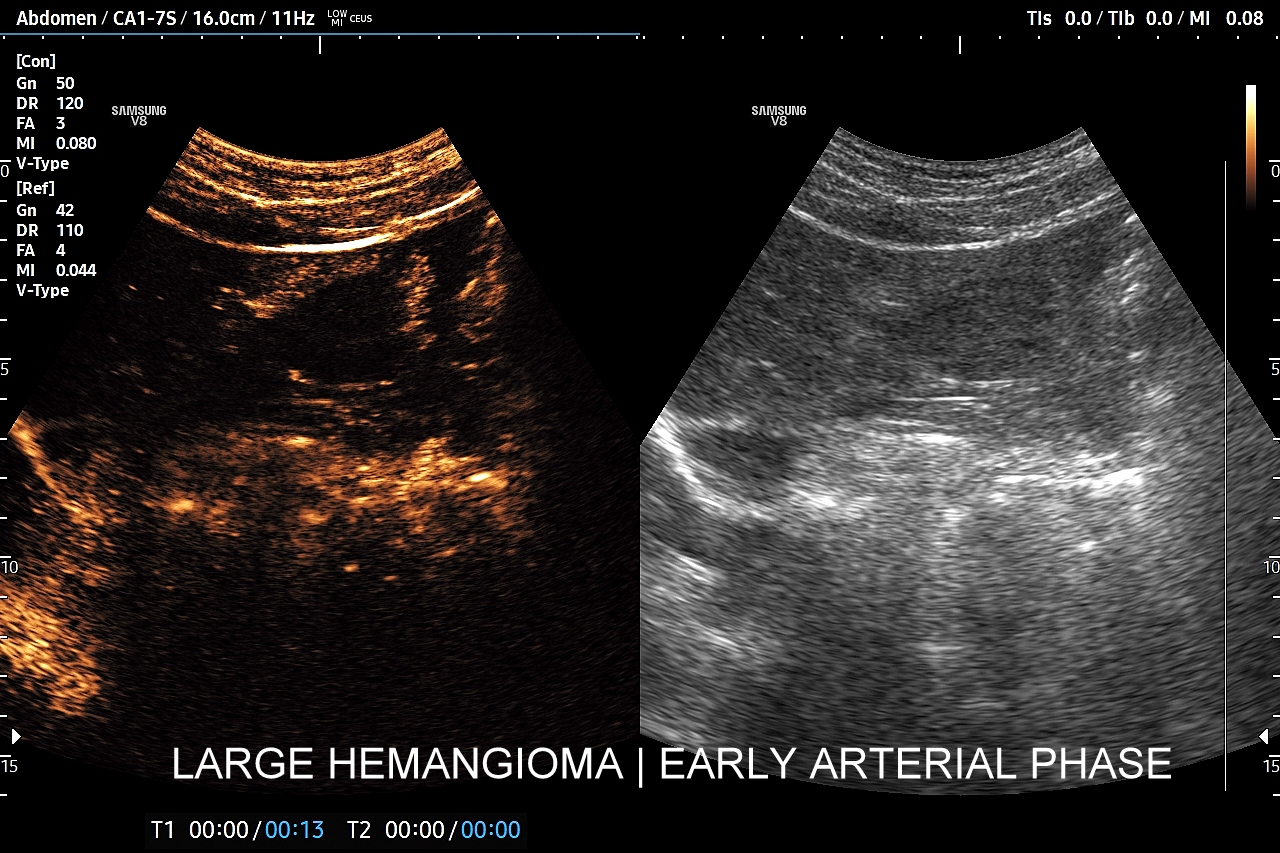

Najbardziej charakterystyczną cechą naczyniaka wątroby w badaniu CEUS jest jego wypełnianie w postaci guzkowej (ang. peripheral nodular enhancement) od obwodu ku centrum zmiany (ang. centripetal). Szybkość wypełniania bywa różnorodna, może być powolna lub szybka. W przypadku szybkiego wypełniania (tzw. flash-filling), w celu wykazania charakterystycznego centrypetalnego wypełniania niezbędna może być postprocessing’owa analiza poklatkowa zapisanego nagrania badania. W fazie późnej naczyniak wątroby pozostaje izowzmocniony lub hyperwzmocniony w stosunku do natywnego miąższu wątroby.

W przypadku dużych naczyniaków obszary, które uległy wykrzepianiu pozostają awaskularne przez wszystkie fazy badania CEUS, tj. nie wypełniają się kontrastem (nonenhancing). W przeciwieństwie do powyższego konstelacja, w której to w fazie wczesnej pojawia się wzmocnienie, a następnie w fazie wrotnej lub późnej ulega wypłukaniu (hypoenhancement) świadczy o cechach złośliwych diagnozowanej zmiany ogniskowej w wątrobie i wyklucza rozpoznanie naczyniaka.